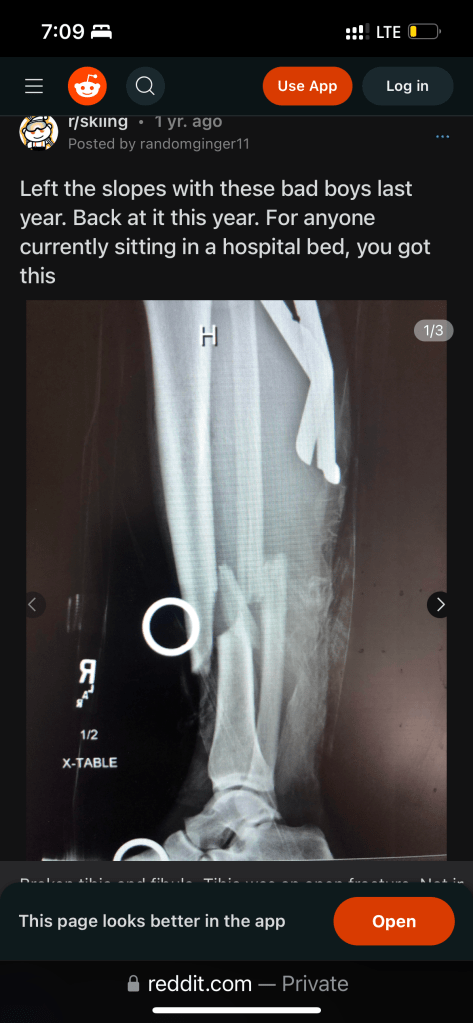

The disability? I had a ski accident after five minutes of enjoying the beautiful powdery green run up in Whistler, broke my right leg, was rushed to the hospital, had a surgery where a titanium rod was inserted in my tibia (bone), and now hopping around on one leg with the help of crutches.

Two, I want to remind myself that time heals all wounds. It might take me another 5 months or more to walk normally again and go back to all the physical activities I’ve missed, but the important thing is — I will heal. I didn’t see my own leg x-ray but I was told my bones shattered like glass. So I googled ski accidents with tibia and fibula fracture while lying in the hospital bed waiting for my surgery schedule. An x-ray of a fractured leg popped out and that gave me a lot of hope for my recovery.